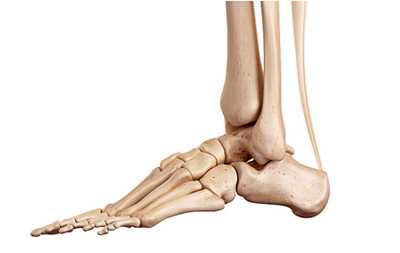

Стопа состоит из 28 костей и 34 суставов, из них 18 выпукло-вогнутые и 16 плоские. Все кости объединены в предплюсну, плюсну и пальцы. Кости предплюсны следующие: таранная, пяточная, кубовидная, ладьевидная, 1, 2, 3 клиновидные; кости плюсны: 1, 2, 3, 4 и 5. Все пять пальцев содержат 14 костей: у большого пальца имеется 2 фаланги, а у 2, 3, 4 и 5 пальцев — по 3 фаланги. Положение стопы в кинематической цепи нижней конечности связано с положением голени. Во время роста скелета вальгус стопы и низкий свод способствуют вторичному повороту бедра и коленного сустава во внутрь. После окончания роста высота свода и угол между большеберцовой и пяточной костями влияют на положение оси коленного сустава во фронтальной плоскости. Чем ниже свод стопы, тем больше ее вальгус, тем сильнее вальгус коленного сустава и тем сильнее наклонена голень во внутрь. Вальгус способствует пронации стопы, растяжению связок по внутренней поверхности коленного и голеностопного суставов, а также подошвенного апоневроза, что влияет на функцию всей нижней конечности.

![]() | Рис. 1. Стопа, вид снаружи. Вилка голеностопного сустава удерживает таранную кость, под которой расположена пяточная кость, соединенная спереди с кубовидной костью |

Кости стопы формируют продольную и поперечную арки или своды. Продольная арка находится в сагиттальной плоскости и имеет протяженность от пяточного бугра до плюсне-фаланговых суставов. Продольный свод стопы состоит из внутренней и наружной арок. Внутренняя арка включает в себя 5 костей: пяточная, таранная, ладьевидная, 1 клиновидная и 1 пястная. Наружная арка состоит их трех костей: пяточная, кубовиидная, 5 плюсневая. Свод имеет форму арки, которая образована жесткими костными полудугами и основанием в виде подошвенного апоневроза.